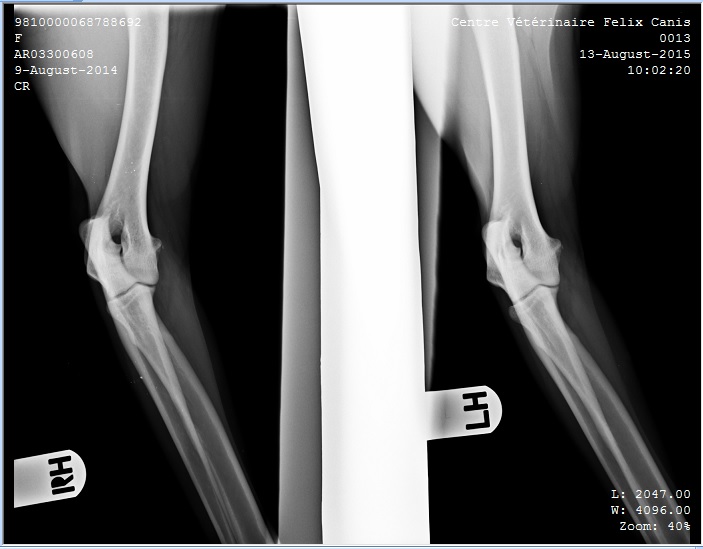

Alexa 2 Published August 14, 2015 at 703 × 549 in Hip and Elbow X-ray’s Keith and Alexa ← Previous Next → Alexa